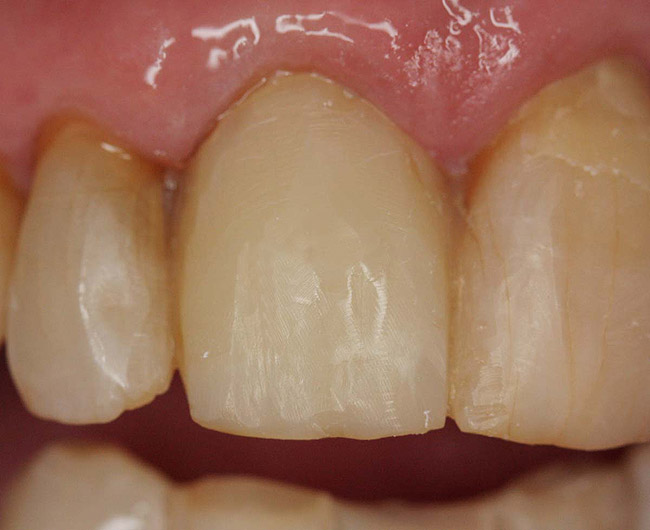

Case 1

A Class IN maxillary bicuspid was previously restored with a fiber post and an all-porcelain crown (Figure 1). The forces of the oral environment resulted in fracture of the fiber post and crown failure. The remaining fiber post in the root was removed, and anti-rotational areas were prepared for a cast post (Figure 2). A gold cast post was constructed at a dental laboratory, using an indirect technique (Figure 3). A porcelain-fused-to-metal (PFM) crown was constructed with a bevel finish to provide a ferrule and reduce forces on the post (Figure 4 and Figure 5).

Figure 1  X-ray of an endodontically treated second bicuspid restored with a fiber post, core, and all-porcelain crown.

Figure 1

Figure 2  Same second bicuspid as Figure 1 after removal of the fractured fiber post.

Figure 2